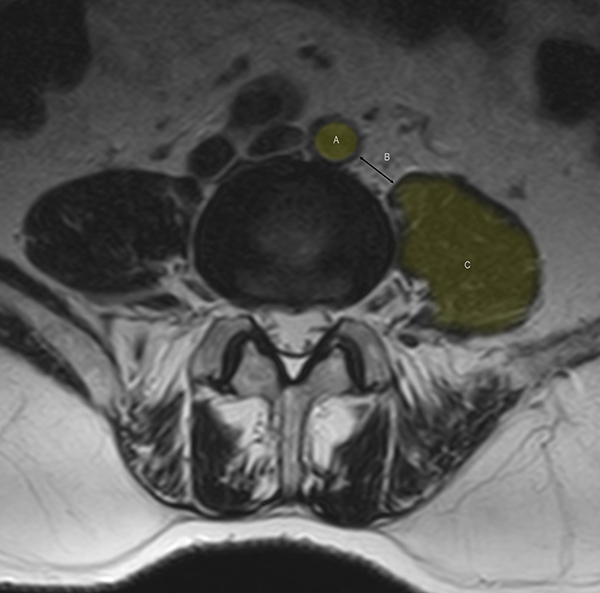

La factibilidad técnica de realizar el OLIF debe ser analizada en las imágenes preoperatorias. En el lado izquierdo de la columna lumbar, el corredor quirúrgico está limitado hacia medial por el borde de la aorta o la arteria iliaca izquierda y hacia lateral por el borde anterior del psoas (corredor o hiato OLIF). Si la distancia entre estas estructuras es menor a 1 cm, el riesgo vascular y la retracción necesaria sobre el psoas aumentan significativamente, por lo que se sugiere optar por una técnica diferente de fusión5 (Figura 2). Esta determinación puede realizarse mediante la medición en los cortes axiales del espacio discal en resonancia magnética (RMN) o tomografía computada (TC) sea en posición convencional o colocando al paciente en posición quirúrgica cuando se realiza el estudio.6 La vena iliolumbar o la vena ilíaca izquierda pueden ser identificadas en el fondo del corredor en el espacio discal L4-5. Cuando esto sucede, sugerimos evitar este abordaje, ya que la movilización de las mismas suele ser riesgosa y dificultosa. Una situación similar se da en los casos de anatomía transicional de la región lumbosacra, donde se modifica la división de los grandes vasos y habitualmente la localización de la vena iliolumbar.

Figura 2: Reconocimiento en imágenes (RMN) del espacio de trabajo en la técnica OLIF a niel L4-L5. A: Arteria Ilíaca izquierda, B: corredor OLIF. C: músculo psoas. Se sugiere un espacio entre A y C mayor a 1 cm.